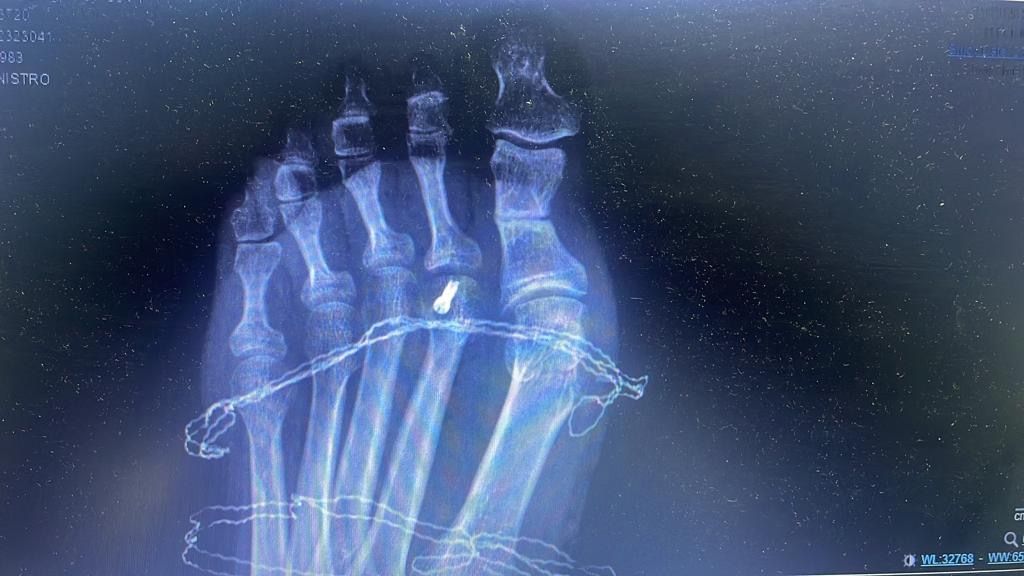

Esistono numerose tecniche chirurgiche, attualmente la più accreditata è l’intervento mini invasivo S.E.R.I. che prevede la correzione dell’osso mediante il posizionamento di un filo, che verrà rimosso a guarigione avvenuta.